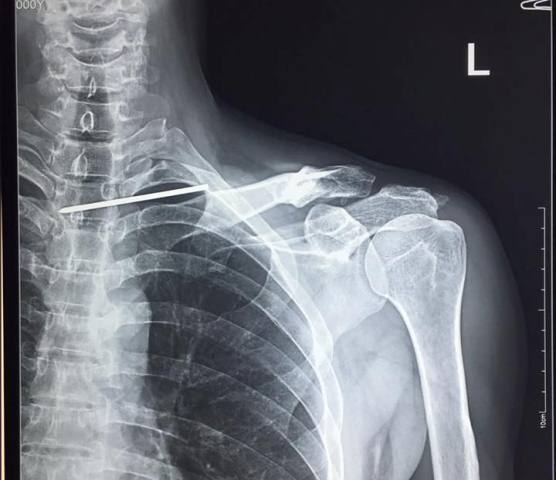

Trao đổi với PV , BS. Trần Trung Kiên - Trưởng khoa Chấn thương chỉnh hình, BVĐK Đức Giang cho biết, trường hợp bệnh nhân này vô cùng đặc biệt, bệnh nhân bị một chiếc đinh Kirschner (K-wire) dài 12cm di chuyển từ phần đầu ngoài xương đòn chạy xuyên qua đỉnh phổi xuyên thẳng vào tuỷ sống. Điều kì lạ là bệnh nhân không hề có bất cứ một dấu hiệu tổn thương thần kinh, vẫn sinh hoạt bình thường mà không hề hay biết về mức độ nguy hiểm của mình.

Hình ảnh chiếc đinh khổng lồ qua phim chụp X-quang.